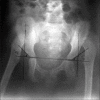

Cutis laxa is a heterogeneous group of diseases, with loose, wrinkled skin folds and hyperelasticity of the skin. There are overlapping of clinical features of the group of syndrome associated with cutis laxa, including congenital cutis laxa, wrinkly skin syndrome and gerodermia osteodysplastica. All these conditions present a challenge to the clinician. Thus, molecular diagnosis is the only way to resolve these phenotypically similar conditions. We hereby describe two Indian patients with wrinkled skin and mild craniofacial dysmorphic features who had molecular confirmation of autosomal recessive cutis laxa.